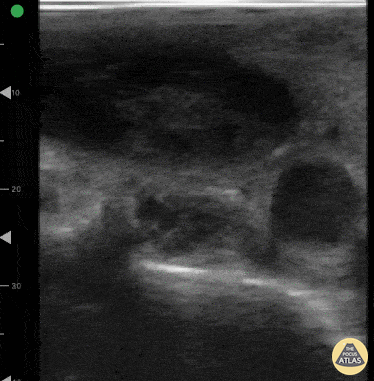

A 27-year-old women presented to ED with acute onset of dyspnea and chest pain. She was hypoxic with an O2 saturation of 91% on room air and tachycardic. POCUS lung ultrasound revealed an A-line pattern bilaterally and was notably absent for pleural effusions. Venous scan of the proximal right femoral region revealed a non-compressible femoral vein with hypoechoic material within the lumen. High resolution chest CT confirmed diagnosis of PE. Dr. Victor Bang. Emergency Physician at Hospital das Clínicas de Marília. Co-founder of Pocus Jedi. @vmjbang